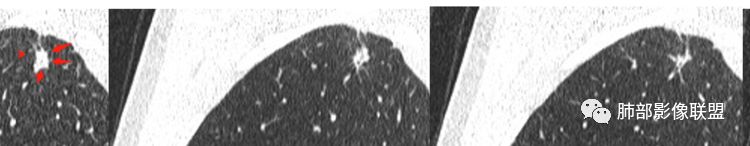

首先病灶是实性?还是GGN?实性我们就按实性的思路走。密度均匀;

形态如何?三角形

边缘整体U型凹陷、平直

边缘长索条

不踏实的地方就是内部支气管部分区域不规整

2.右肺上叶胸膜下不规则实性密度小结节影,密度均匀。边界清楚,缺乏典型深分叶,除个别层面上圆隆外,大多边缘平直甚至内凹,成三角形轮廓,冠状位甚至状如“奔驰”车标。

3.可见棘状突起或条索影牵于胸膜间,胸膜侧可见毛刺。灶周未见磨玻璃影。